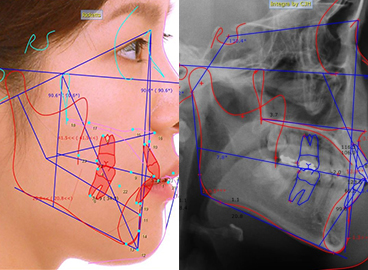

• 인공지능 (AI)을 활용한 치아교정 시뮬레이션 시스템

세계적 교정 진단 분석 프로그램으로 교정 전 진단과 성장 분석, 예측, 악교정 진단이 가능한 정밀 분석 프로그램입니다.

• 미리 보는 결과

교정 전, 후 시뮬레이션을 타임랩스 영상으로 확인 가능

• 다양한 임상사례 구성 방식

임상사례를 보다 다양하게 적용해볼 수 있는 장점

• 디테일한 치료 계획

다양한 분석 방법으로 디테일한 치료 계획 수립 가능